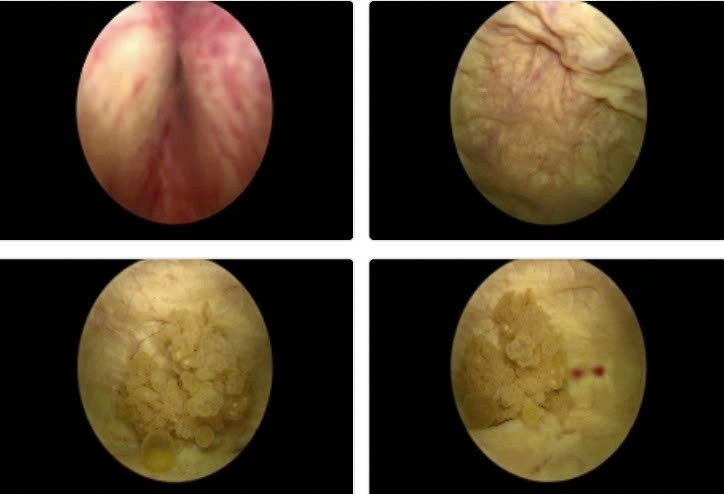

Hình ảnh nội soi u bàng quang vị trí sát lỗ niệu quản trái kích thước 2cm, có chỉ định phẫu thuật nội soi cắt u bàng quang sớm để chẩn đoán tế bào học - Ảnh BVCC

ut-bang-quang.jpg